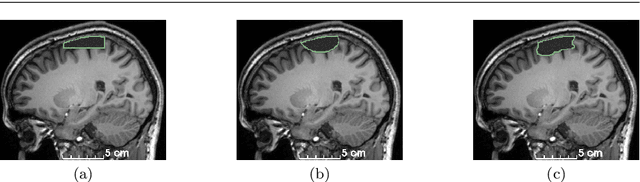

Abstract:Accurate segmentation of brain resection cavities (RCs) aids in postoperative analysis and determining follow-up treatment. Convolutional neural networks (CNNs) are the state-of-the-art image segmentation technique, but require large annotated datasets for training. Annotation of 3D medical images is time-consuming, requires highly-trained raters, and may suffer from high inter-rater variability. Self-supervised learning strategies can leverage unlabeled data for training. We developed an algorithm to simulate resections from preoperative magnetic resonance images (MRIs). We performed self-supervised training of a 3D CNN for RC segmentation using our simulation method. We curated EPISURG, a dataset comprising 430 postoperative and 268 preoperative MRIs from 430 refractory epilepsy patients who underwent resective neurosurgery. We fine-tuned our model on three small annotated datasets from different institutions and on the annotated images in EPISURG, comprising 20, 33, 19 and 133 subjects. The model trained on data with simulated resections obtained median (interquartile range) Dice score coefficients (DSCs) of 81.7 (16.4), 82.4 (36.4), 74.9 (24.2) and 80.5 (18.7) for each of the four datasets. After fine-tuning, DSCs were 89.2 (13.3), 84.1 (19.8), 80.2 (20.1) and 85.2 (10.8). For comparison, inter-rater agreement between human annotators from our previous study was 84.0 (9.9). We present a self-supervised learning strategy for 3D CNNs using simulated RCs to accurately segment real RCs on postoperative MRI. Our method generalizes well to data from different institutions, pathologies and modalities. Source code, segmentation models and the EPISURG dataset are available at https://github.com/fepegar/ressegijcars .